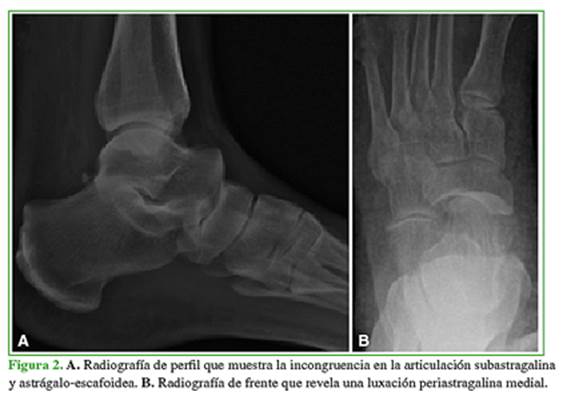

Las radiografías revelaron una luxación periastragalina medial, con evidente incongruencia de las articulaciones astrágalo-escafoidea y astrágalo-calcánea (Figura 2). La tomografía computarizada no mostró lesiones óseas asociadas (Figura 3).